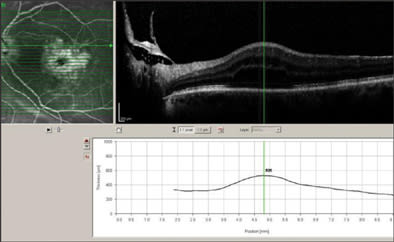

Effective treatment depends on an understanding of the pathophysiology and having an effective armamentarium to treat the underlying cause. Currently, our most effective treatment strategies involve either relief of vitreoretinal traction or epiretinal membranes in conjunction with a growing number of effective anti-inflammatory drugs. Pretreatment evaluation should include a careful history, including duration of symptoms and the presence of any comorbid illness such as diabetes. Slit-lamp examination to evaluate for the presence of anterior vitreous prolapse, iris trauma, or a peaked or irregular irides is mandatory. Careful examination of the macula to note the presence or absence of an epiretinal membrane, vitreomacular traction, or the presence of diabetic retinopathy may be helpful in stratifying the risk of CME and planning a treatment strategy. Diagnostic testing, in particular OCT and fluorescein angiography, should be performed to confirm the diagnosis, but also to rule out any macular pathology that may have been missed during funduscopic evaluation (Figure 3).

Figure 3. Confirmation of CME diagnosis on OCT.